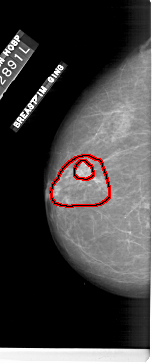

A_1174_1.LEFT_CC

FILE: A_1174_1.LEFT_CC.OVERLAY

TOTAL_ABNORMALITIES 1

ABNORMALITY 1

LESION_TYPE MASS SHAPE IRREGULAR MARGINS SPICULATED

ASSESSMENT 5

SUBTLETY 4

PATHOLOGY MALIGNANT

TOTAL_OUTLINES 2

BOUNDARY

CORE